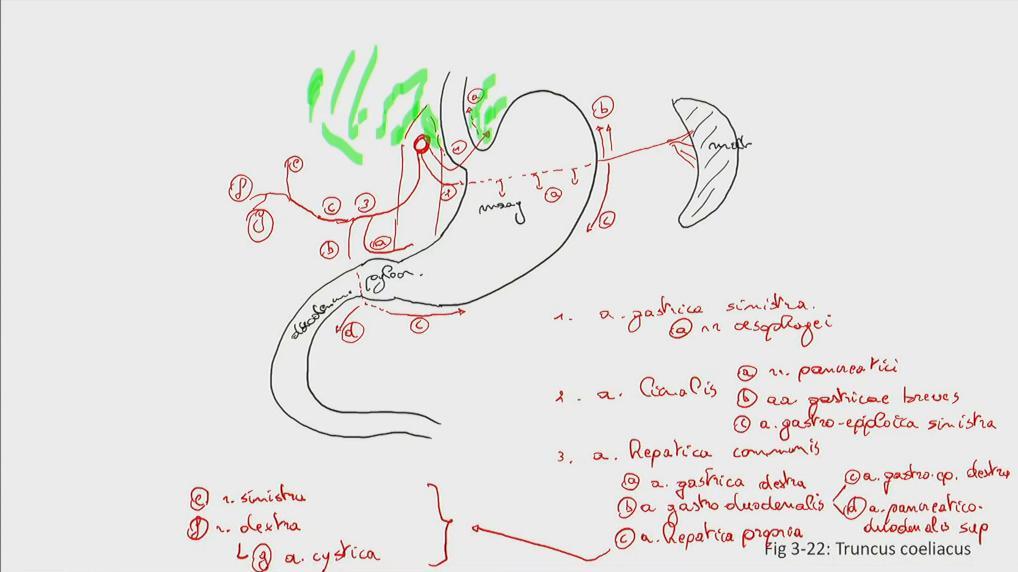

Fig 3.22: tr. coeliacus

diaphragma (groen) oesophagus -

ventriculus = maag

duodenum milt -

aorta abdominalis

|

|